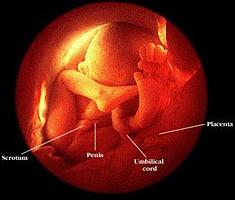

Eighteen week pre-born baby

The fetus is now about 5 inches long. The child blinks, grasps,

and moves her mouth. Hair grows on the head and body.

20 weeks - The child can hear

and recognize mother's voice. Though still small and fragile, the

baby is growing rapidly and could possibly survive if born at this

stage. Fingernails and fingerprints appear. Sex organs are visible.

Using an ultrasound device, the doctor can tell if the child is a

girl or a boy. The one on the left is a baby girl.